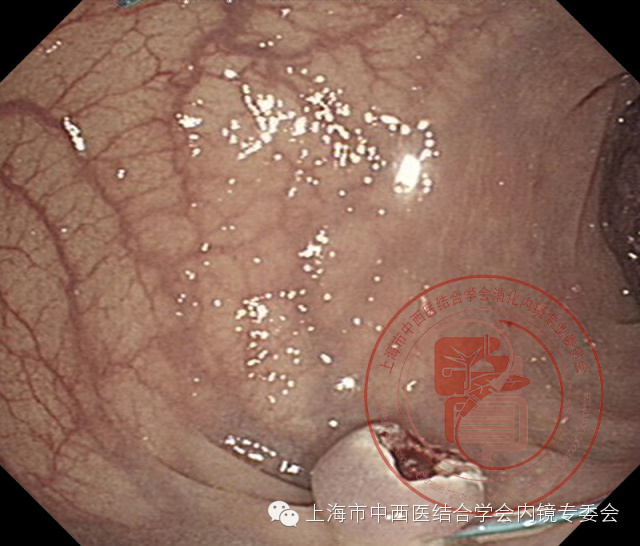

带蒂息肉尼龙套扎操作

内镜抵达病变区域时,仔细观察息肉蒂部,如果蒂径<1.2cm,不宜用尼龙圈套器,因收紧时容易切割蒂部,引起大出血。尼龙圈套器对准隆起病变基部套入,确认尼龙圈套线距肠壁5mm处,嘱助手缓慢推出塑料外套管并接近蒂部,紧接着一边缓慢朝助手方向拉移塑料外套管,一边缓慢收紧释放装置,这时可以看到塑料外套管内的塑料固定器向前推移,使尼龙圈套器逐渐缩小,直至收紧息肉蒂部,明确息肉蒂部血供被阻断(病变表面色泽由橘红变暗红或紫红色为止)后,随后朝助手方向快速拉移塑料外套管,尼龙圈套器尾端与金属拉钩之间迅速脱离,退出释放装置。金属圈套线距尼龙圈套线上5mm处收紧后进行高频电切除,避免离尼龙圈套线太近,术后尼龙圈套容易脱落,引起大出血。过长的尼龙尾线可以用缝合线剪切器剪去,但注意不宜剪的过短,避免尼龙圈套线从塑料固定器中滑脱,并发大出血。

带蒂息肉

阻断蒂部血供

切除后创面